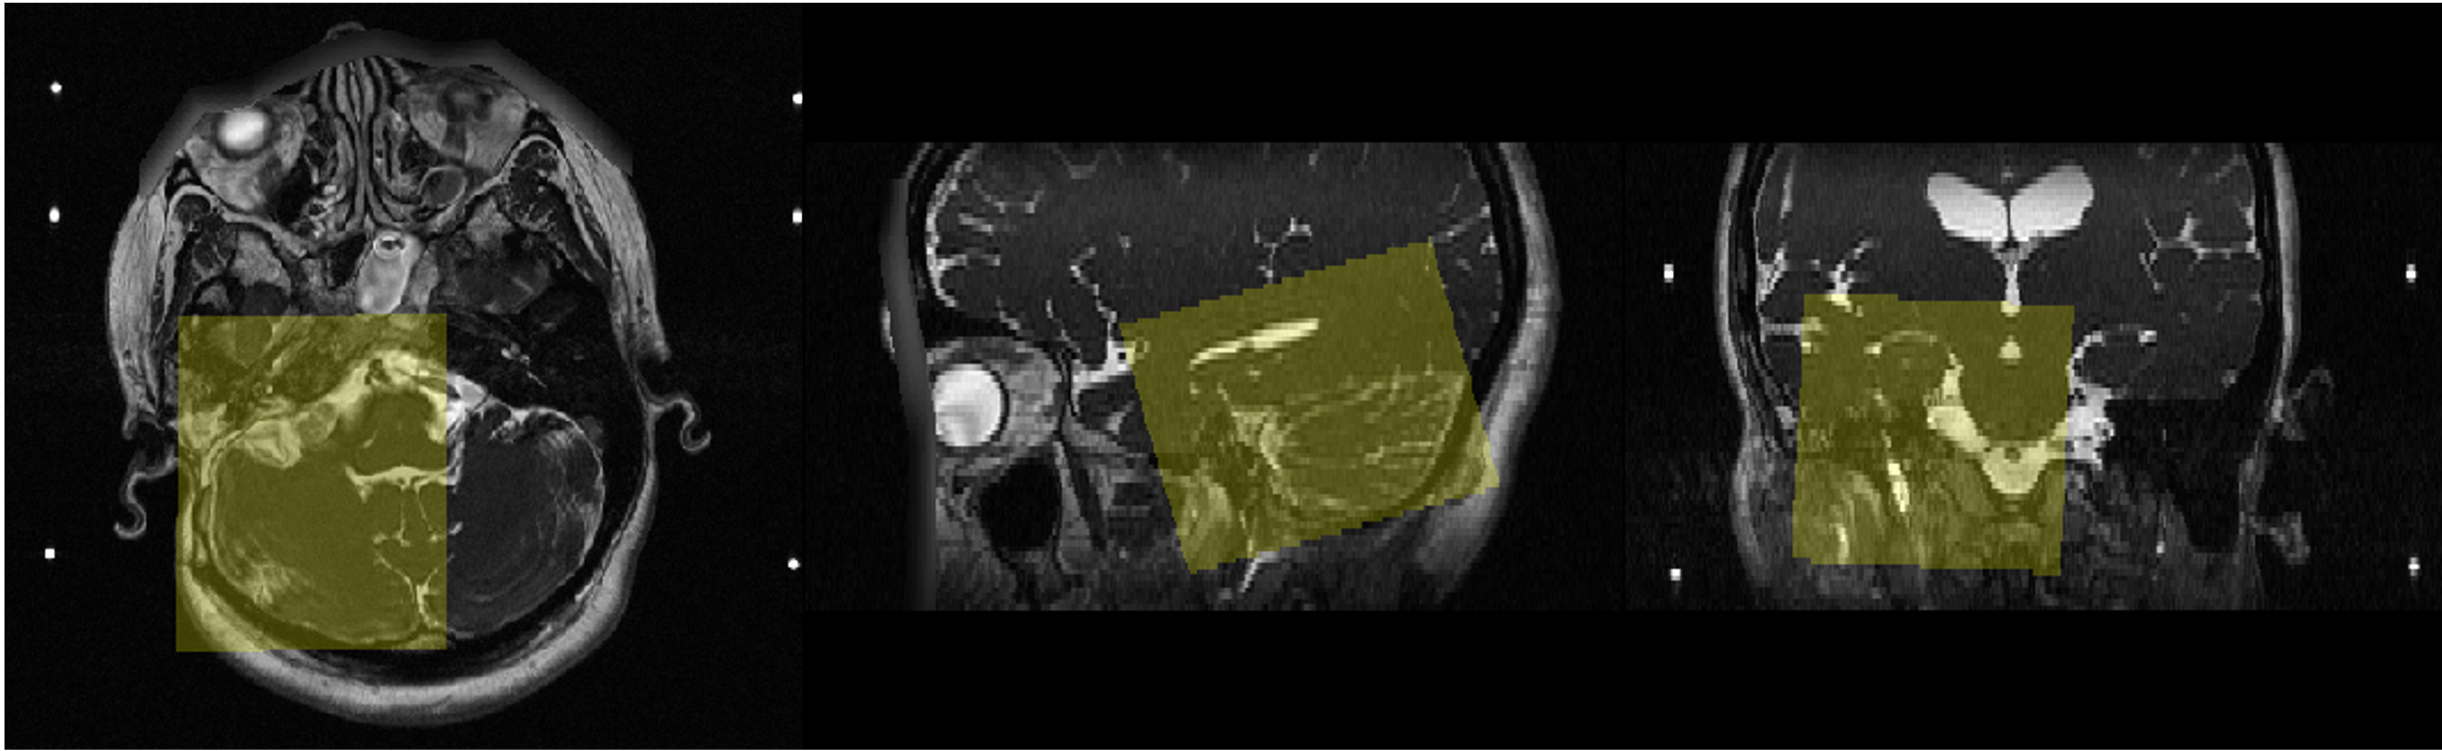

3.2 Data and Implementation

The dataset was released by the MICCAI challenge crossMoDA 2021 [16]. All images were obtained on a 32-channel Siemens Avanto 1.5T scanner using a Siemens single-channel head coil [17]. ceT1 images have in-plane resolution of 0.41×0.41 mm and slice thickness of 1.0 or 1.5 mm. For hrT2 images, the in-plane resolution varies from 0.47×0.47 mm to 0.55×0.55 mm and slice thickness is 1.0 or 1.5 mm. The VS and cochleae were manually segmented in consensus by the treating neurosurgeon and physicist using both the ceT1 and hrT2 images. We randomly split the images into 185 and 25 for training and validation respectively. Since the Field of View (FoV) of the source and target domain images varies significantly, we crop each image into a cubic box, or ROI, using single-atlas registration [18]. As shown in Figure 2, the ROI on the atlas image is manually cropped around the right side of the brain. To obtain the ROI on the left side, we flip the volume left-to-right before performing registration.

Refer to caption

Figure 2: An illustration of our cropped ROI on the target domain atlas image.